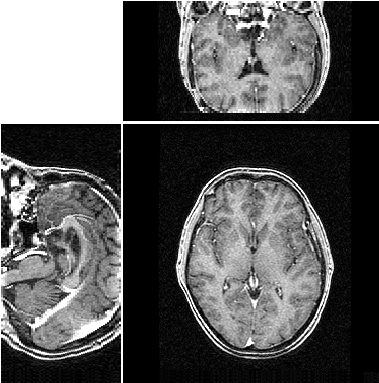

Dans le cadre du projet AGIR, l'équipe Rainbow s'intéresse à la comparaison d'algorithme de recalage d'images 3D. Le recalage d'images consiste à aligner différentes images pour les faires coincider au mieux:

| ![]() | |

| sans recalage | avec recalage |

Ces algorithmes sont coûteux en calculs et l'utilisation de grille de calcul a permis de tester plusieurs algorithmes existants sur des grandes bases de données. Cependant, seule des méthodes utilisant des transformations globales des images ont été utilisées. Ces transformations correspondent pas exemple au fait qu'un patient a pu bouger la tête au cours d'une acquisition IRM. Lorsque l'on veut comparer des images prises à des époques différentes ou bien comparer des images issus de plusieurs patients, ces transformations globales ne suffisent plus: il faut également tenir compte de transformations locales: